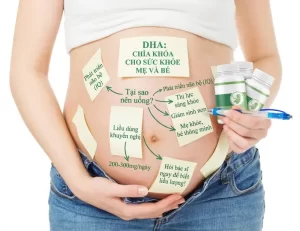

Có nên uống DHA khi mang thai không? Lợi ích và cách bổ sung đúng

Thiếu DHA khi mang thai có nguy hiểm không? 7 ảnh hưởng mẹ bầu cần biết sớm

Dinh dưỡng cho mẹ bầu: Ăn gì tốt cho thai nhi, thực đơn theo từng giai đoạn thai kỳ.